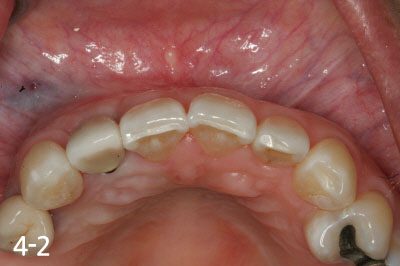

Implant crown is fabricated after successful bone graft and implant placement